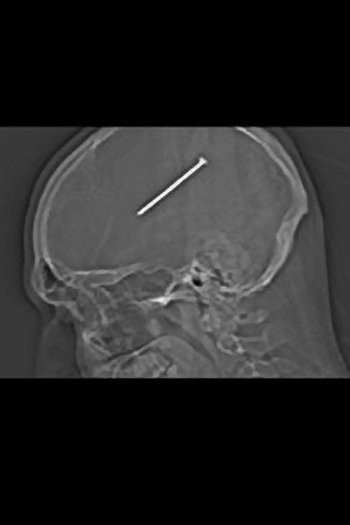

3. Paku Masuk ke Otak

Ketika merasa ada yang tidak beres, dia memeriksakan diri ke rumah sakit dan terkejut melihat hasil rontgen. Paku sepanjang 8,25 mili berdiam di dalam otaknya. Beruntung paku ini tidak menimbulkan kerusakan parah dan dapat diambil oleh dokter.